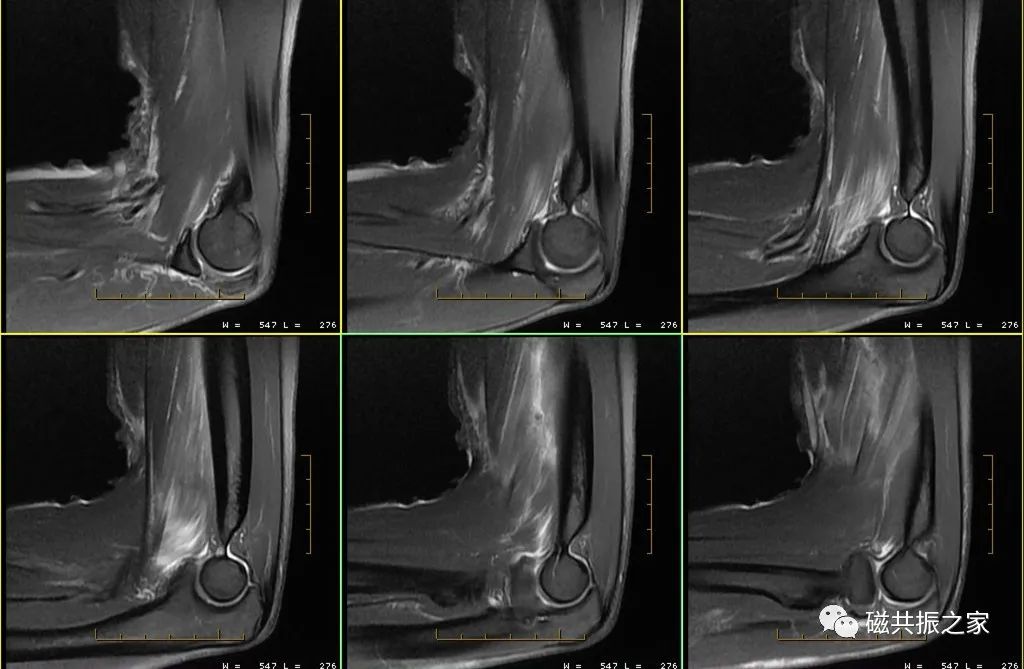

• 肘部韧带和肌腱损伤的MRI诊断

肘部韧带和肌腱损伤的MRI诊断